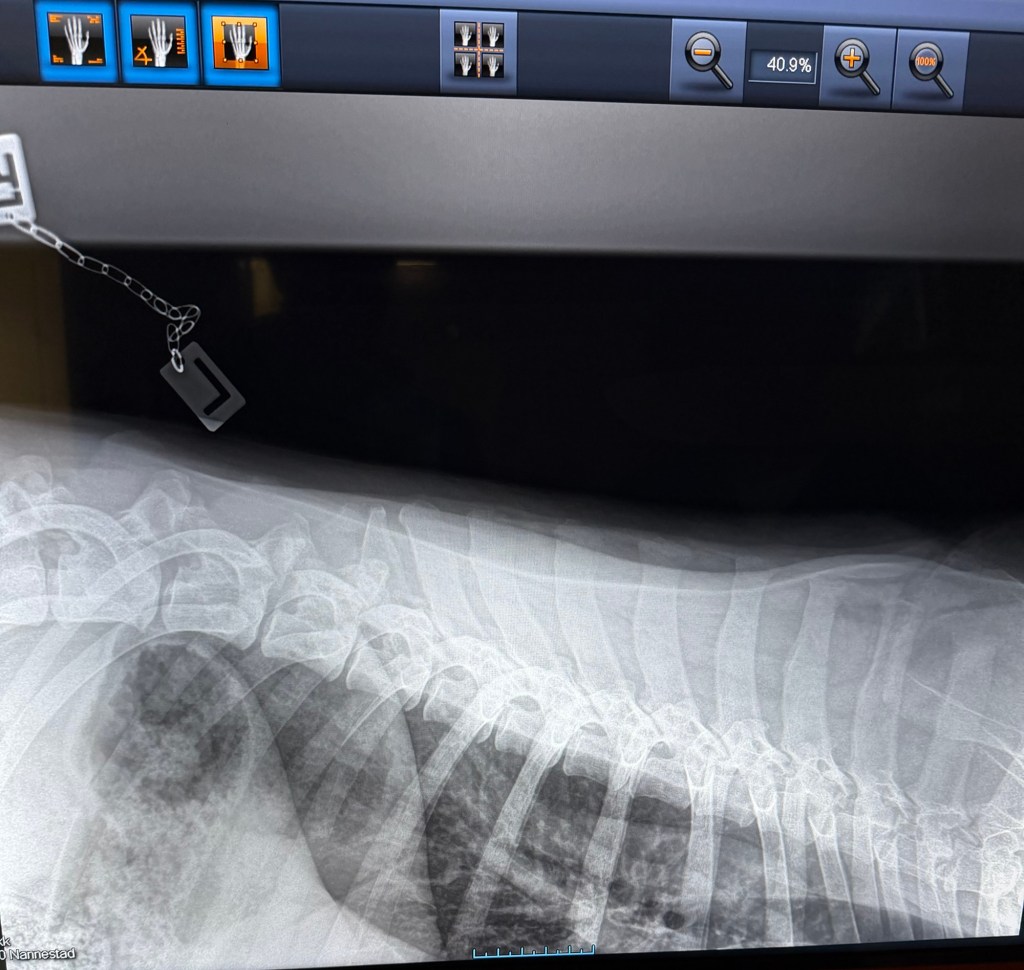

Geri var på ny røntgen nå i november 2025, i en alder av 3år og 8måneder. Dette for å være ansvarlig og forsikre meg om at det ikke blir avl på foreldredyr som har feil utvikling og avdekke svakheter hvis de eksisterer.

Det viste seg å være meget positive resultater (legger ved noen av bildene). Ingen forkalkninger og fremdeles fine albuer, ingen forandring fra 18 måneder HD/AD røntgen til nesten 4års alder. Hun har også en meget fin rygg, og spesielt god og robust lenderygg (bak) som er et fokus område for schæferhunden.